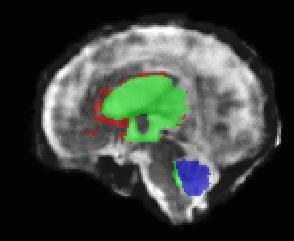

Limiting failures of machine learning systems is of paramount importance for safety-critical applications. In order to improve the robustness of machine learning systems, Distributionally Robust Optimization (DRO) has been proposed as a generalization of Empirical Risk Minimization (ERM). However, its use in deep learning has been severely restricted due to the relative inefficiency of the optimizers available for DRO in comparison to the wide-spread variants of Stochastic Gradient Descent (SGD) optimizers for ERM. We propose SGD with hardness weighted sampling, a principled and efficient optimization method for DRO in machine learning that is particularly suited in the context of deep learning. Similar to a hard example mining strategy in practice, the proposed algorithm is straightforward to implement and computationally as efficient as SGD-based optimizers used for deep learning, requiring minimal overhead computation. In contrast to typical ad hoc hard mining approaches, we prove the convergence of our DRO algorithm for over-parameterized deep learning networks with ReLU activation and a finite number of layers and parameters. Our experiments on fetal brain 3D MRI segmentation and brain tumor segmentation in MRI demonstrate the feasibility and the usefulness of our approach. Using our hardness weighted sampling for training a state-of-the-art deep learning pipeline leads to improved robustness to anatomical variabilities in automatic fetal brain 3D MRI segmentation using deep learning and to improved robustness to the image protocol variations in brain tumor segmentation. Our code is available at https://github.com/LucasFidon/HardnessWeightedSampler.